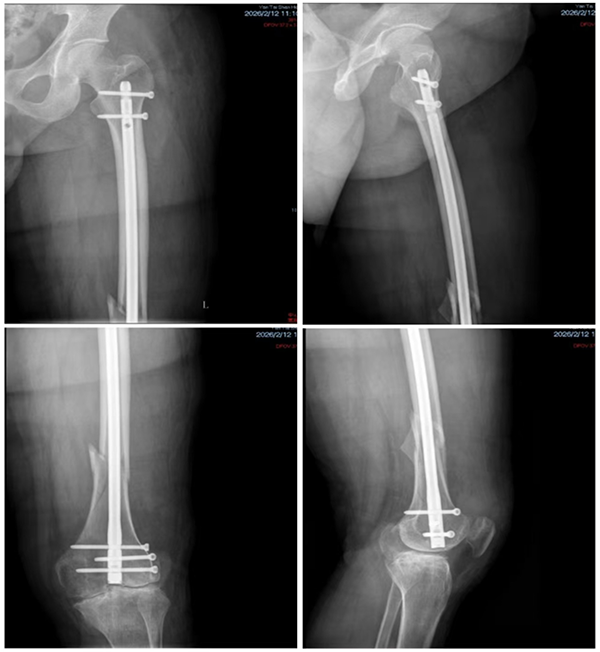

在陈明齐的统筹协调下,血液科团队全程精准指导患者接受凝血因子输注治疗。经过3天规范诊疗,患者凝血四项指标均恢复正常,凝血因子活性达到手术安全标准,手术时机完全成熟。2月11日,多学科团队组成的手术小组正式为李先生实施手术,术中精准运用加压止血带、分层切开、精细创面止血等技术,采用“间接复位+器械微创直接复位”相结合的方式,精准恢复骨折部位对位对线,同时通过扩髓髓内钉进行稳定固定,术后做好充分引流与严密缝合,全程实现精准操作、严格控血。整个手术过程顺利有序,未发生任何手术并发症。

在圆满完成手术的同时,也最大程度上减少了术中出血量